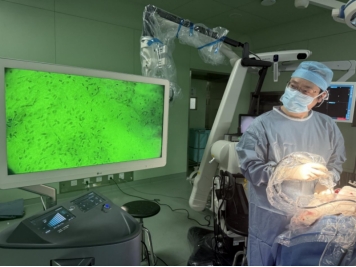

÷„ЅцЌвњ∆ ÷ х≥§∆Џ√жЅў°∞±яљз≈–ґ®°±µƒћф’љ°™°™÷„ЅцѕЄ∞ы‘Џ ÷ х÷–њі∆рјі”л’э≥£ѕЄ∞ыЈ«≥£ѕаЋ∆£ђѕ÷”–ЉЉ хƒ—“‘Ј÷±ж°£Єіµ©іу—ІЄљ фї™…љ“љ‘Ї√Ђ”±‘Ї≥§÷Є≥ц£Ї°∞ ÷ х≤їљцљц ««–≥э÷„Ѕц£ђќ“√«µƒƒњ±к «‘ЏЊ°њ…ƒ№±£Ѕф÷№ќІљ°њµ„й÷ѓµƒЌђ ±£ђ≥єµ„µЎ«е≥э÷„ЅцѕЄ∞ы°£°±°∞Њ°є№µЉЇљѕµЌ≥ЇЌ”Ђєв≥…ѕсЉЉ хћбЄяЅЋ х÷–≥…ѕсµƒЊЂ„Љґ»£ђµЂ’в–©є§Њя»‘»їƒ—“‘«еќъѕ‘ Њ…о≤њ≤°‘оїт√ч»ЈќҐ–°µƒ÷„Ѕц±яљз°£°±“тіЋ£ђЎљ–иƒ№єї‘Џ ÷ хєэ≥ћ÷–«шЈ÷÷„ЅцѕЄ∞ыЇЌ’э≥£ѕЄ∞ыµƒЉЉ х£ђ“‘∞п÷ъЌвњ∆“љ…ъ µ ±„ц≥цЄь√ч÷«µƒЊц≤я°£EndoSCell?„чќ™»Ђ«тµЏ“їЄц“≤ «ќ®“ї“їЄц”√”Џ∞©÷ҐЉм≤вµƒѕЄ∞ыЉґ”ЂєвµЉ“э≥…ѕсЉЉ х£ђ „іќ»√Ќвњ∆“љ…ъ‘Џ х÷– µ ±≤ґ„љµљѕЄ∞ыЉґЌЉѕс£ђљЂ х÷–њ… ”їѓЊЂґ»і”„й÷ѓЉґћб…э÷Ѕ—«ѕЄ∞ыќђґ»°£Є√ЉЉ хЌї∆∆»в—џ ґ±р”лЇЅ√„Љґ”∞ѕсµƒќпјнЊ÷ѕё£ђњ™ііЅЋїщ”Џ—«ѕЄ∞ыњ… ”їѓµƒЊЂ„Љ ÷ х ±іъ°£Є√…и±Є”Џ2023ƒкїс÷–єъNMPAґюја“љЅ∆∆ч–µ»ѕ÷§£ђѕ÷“—±ї»Ђєъ∞ьј®ї™…љ“љ‘Ї‘ЏƒЏµƒ40”аЉ“ґ•Љв“љ‘Їƒ…»л ÷ хЅч≥ћ£ђЅўі≤”¶”√≥ђєэ500јэ…сЊ≠Ќвњ∆ ÷ х°£

EndoSCell?µƒµЃ…ъ‘і”Џіі Љ»Ћљѓјс—ф≤© њ2012ƒк‘Џ∞ЎЅ÷¬нњЋЋє°§µ¬ґы≤Љ¬јњЋ÷––ƒµƒњ∆—–ґі≤м°£"іЂЌ≥ѕ‘ќҐЊµќёЈ® ”¶ґѓћђ ÷ х≥°Њ∞£ђќ“√«Ќ®єэќҐ–Ќїѓєв—ІѕµЌ≥”лєв—ІЈјґґЉЉ хµƒ»ЏЇѕ£ђљЂќпЊµµƒ÷±ЊґЋх–°µљљц3ЇЅ√„£ђ ”“∞÷±ЊґЌЎ’є÷Ѕ500ќҐ√„£ђЄяіп1200±ґµƒЈ≈іу±ґ¬ ѕ¬љц”–≤їµљ4ќҐ√„µƒґґґѓ”∞ѕм£ђ„гєїµƒЊЂ„ЉЇЌ±г–ѓ–‘ є∆дƒ№єї”Џ х÷– µ ±‘Џће”¶”√°£°±Є√…и±Є≤…”√”ЂєвµЉ“эЉЉ х£ђ є“љ…ъƒ№‘Џ х÷–њіµљЄя«е°Ґґѓћђ°Ґ µ ±µƒѕЄ∞ыЌЉѕс£ђ”¶”√∆дґ‘Ѕц«їµƒњ…“…«ш”т°Ґ÷Ўµг«ш”тљш––…®≤й£ђњ…∞п÷ъЌвњ∆“љ…ъ÷±љ”»в—џ±ж±р÷„ЅцѕЄ∞ы£ђљшґш µѕ÷ѕЄ∞ыЉґµƒЊЂ„Љ ÷ х°£

Єіµ©іу—ІЄљ фї™…љ“љ‘Ї…сЊ≠Ќвњ∆µƒ≥¬ЅЅљћ Џ±н Њ£Ї°∞ѕ÷‘Џќ“√«њ…“‘‘Џ10Ј÷÷”ƒЏЌк≥…»Њ…Ђ°Ґ…®√иЇЌљвґЅ÷„Ѕц±яљз°£°±°∞Є√ѕµЌ≥ƒ№єїЅҐЉіћбє©ѕЄ∞ыЇЋ°Ґ√№ґ»ЇЌЈ÷≤Љµƒ–≈ѕҐ£ђћбє©ЄьЌк’ыµƒЌЉѕс£ђЌђ ±≤їїбітґѕ ÷ хЅч≥ћ°£°±EndoSCell?µƒ°∞¬ю”ќ љ°±…®√и√÷≤єЅЋ±щґ≥≤°јнµ•µг»°≤ƒ°ҐЇƒ ±≥§µ»≤ї„г£ђƒ№єї»Ђ√ж ґ±рЌвњ∆“љ…ъЇЌ≤°јн—ІЉ““≈¬©µƒ÷„Ѕц„й÷ѓ£ђќ™÷„Ѕц«–≥э ÷ хћбє©ЅЋ“ї÷÷Єьњм°ҐЄь„Љ°ҐЄь»ЂµƒљвЊцЈљ∞Є£ђі”ґшѕ‘÷шћб…эЅЋїЉ’яµƒ÷ќЅ∆–Ієы°£

ЌЉ£ЇЄіµ©іу—ІЄљ фї™…љ“љ‘Ї…сЊ≠Ќвњ∆„®Љ“Ќ≈ґ”‘Џƒ‘љЇ÷ Ѕц ÷ х÷–”¶”√EndoSCell?

іЋЌв£ђї™…љ“љ‘Ї…сЊ≠Ќвњ∆µ»Ќ≈ґ”љь»’ЈҐ±н‘Џ°ґInternational Journal of Surgery°Ј‘”÷Њ…ѕµƒ“ї∆™єЎ”Џƒ‘љЇ÷ Ѕц х÷–«–‘µЊЂ„Љґ®ќїѕаєЎ—–Њњµƒ±®µј÷Є≥ц£ђѕЄ∞ыЉґ”ЂєвµЉ“эЉЉ хґ‘ћеЌвљЇ÷ Ѕц’пґѕµƒ„Љ»Ј¬ Єяіп90.4%£ђґ‘µЉЇљ»Ј»ѕµƒљЇ÷ Ѕц“х–‘±я‘µљш–– х÷–°∞¬ю”ќ љ°±…®√иµƒ„Љ»Ј¬ ќ™94.2%°£∆дЋыѕаєЎ—–Њњ“≤±н√чEndoSCell? х÷–≥…ѕсµƒ’пґѕ„Љ»Ј–‘Ј«≥£Єя£ђњ…”л±щґ≥«–∆ђ≤°јн—Іµƒ„Љ»Ј–‘ѕаж«√ј°£Ѕўі≤ эЊЁЊщ÷ЄѕтEndoSCell?њ…„чќ™±к„Љ÷ќЅ∆µƒЄ®÷ъ ÷ґќ£ђґ‘÷„Ѕц ÷ х«–‘µЉ∞њ…“…«шµƒњмЋўћљ≤й“—іпµљљ”љь„й÷ѓ—І≈–ґѕљр±к„ЉµƒЋЃ∆љ£ђ≥…ќ™ЈмЇѕ«∞µƒ„оЇу°∞∞—єЎ»Ћ°±°£∆д…иЉ∆≥х÷‘÷±їчЌвњ∆÷’ЉЂƒњ±к°™°™Ќї∆∆»в—џЉЂѕё£ђ“‘ѕЄ∞ыЉґЊЂґ» µѕ÷ х÷–÷„Ѕц„й÷ѓґѓћђ„Ј„ў”лЊЂ„Љ«–≥э£ђ÷ъЅ¶Ќвњ∆“љ…ъ‘ЏЄщ÷ќ–‘«–≥э”лє¶ƒ№±£ї§ЉдіпµљќҐ√„Љґ∆љЇв°£’в≤їљцќ™„оіуїѓ∞≤»Ђ«–≥эћбє©ЉЉ х±£’ѕ£ђЄьƒ№Љх«бїЉ’я‘Џ«йЄ–ЇЌ…нће…ѕµƒЄЇµ£°£

EndoSCell?’э‘Џ“эЅмЌвњ∆ ÷ хµƒЈґ љ±дЄп°™°™Ќ®єэ х÷– µ ±ѕЄ∞ыЉґ”ЂєвµЉ“эѕµЌ≥£ђ≥…є¶љЂ÷„Ѕц±яљз≈–ґ®і”ЇЅ√„”∞ѕс ±іъЌ∆љшµљќҐ√„ѕЄ∞ыЉЌ‘™°£“—–ќ≥…Є≤Є«…сЊ≠ѕµЌ≥÷„Ѕц°Ґ»йѕў∞©±£»й°ҐЉ„„іѕў∞©є¶ƒ№±£ї§°ҐќЄ≥¶∞©є¶ƒ№±£ї§°Ґ«∞Ѕ–ѕў∞©є¶ƒ№±£ї§µ»»Ђ≥°Њ∞µƒЊЂ„Љ ÷ хЊЎ’у£ђ‘Џс≤рп‘оћљ≤й°Ґƒ‘—™є№ ÷ х∆јєјµ»Ј«÷„ЅцЅм”т“≤њ™∆фЅЋ»Ђ–¬ќђґ»£ђЌ®єэ х÷–ѕЄ∞ыЉґЌЉѕсЄ®÷ъ“љ…ъґ‘«–‘µЉ∞≤°‘о«ш”тљш––ЊЂ„Љ≈–±р£ђі”ґш‘Џ х÷–„оєЎЉьµƒ ±ЉдЇЌµЎµг„ц≥цЄь√ч÷«µƒЊц≤я°£ќіјі£ђ чЌїЊЂ√№љЂЉ”іуњ∆—–Ѕ¶ґ»£ђљЂEndoSCell?і” µ ±≥…ѕсє§ЊяЈҐ’єќ™ґає¶ƒ№Ќвњ∆∆љћ®°£’э»зљѓјс—ф≤© њЋщ—‘£Ї°∞ чЌїЊЂ√№µƒƒњ±к «ћбє©іпµљ ÷ хЉЂѕёµƒє§Њя£ђ»√√њћ® ÷ хґЉЊЂ„Љµљµ•ЄцѕЄ∞ы£ђ‘ЏЊцґ®–‘ ±њћќ™ х’я„Ґ»лѕ‘ќҐґі≤мЅ¶£ђ„о÷’ µѕ÷∞≤»Ђµƒ“‘Љ∞„оіуїѓµƒ÷„Ѕц«–≥э£ђЉі±£Ѕфє¶ƒ№µƒЌђ ±љЂ÷„Ѕц«–≥эЄ…Њї°£°±